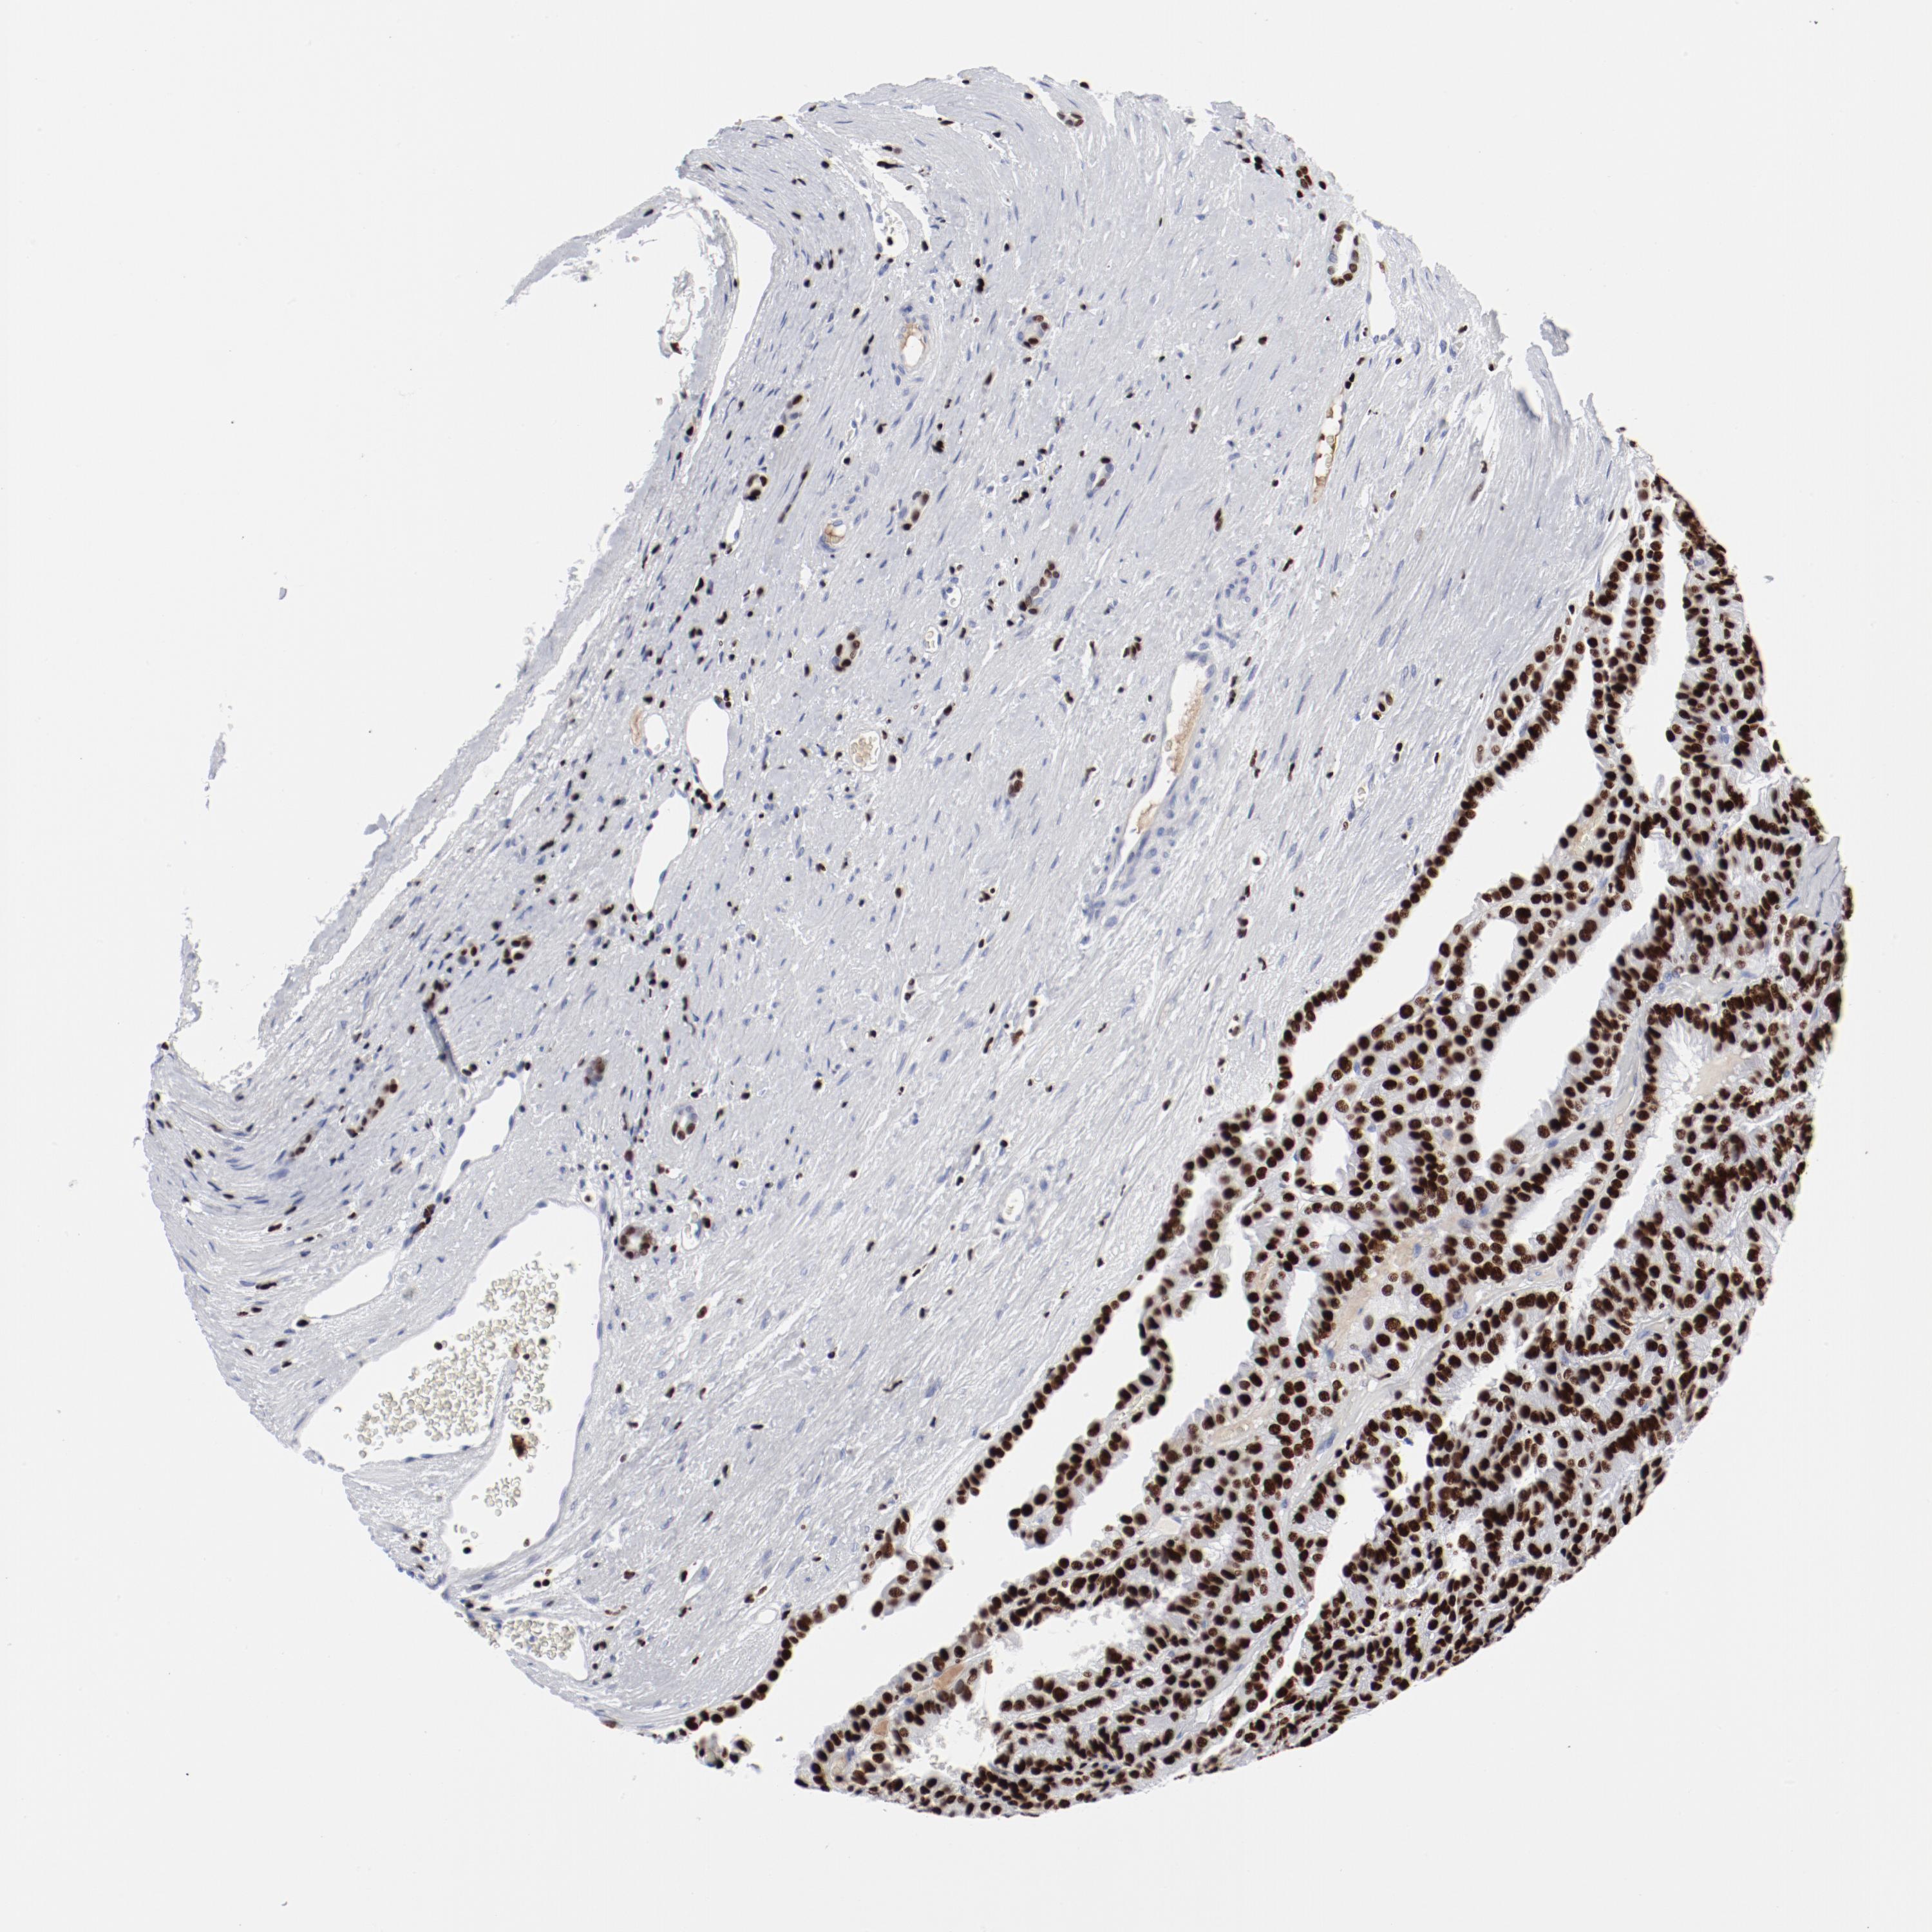

SMARCC2

• SMARCC2